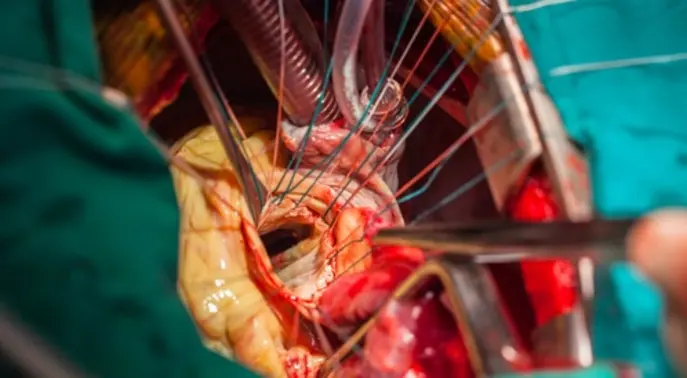

كيف تتم عملية القلب المفتوح؟

تستغرق عملية القلب المفتوح عادة ما بين 3 إلى 6 ساعات، وقد تستمر لفترة أطول حسب تعقيد الحالة. تتم العملية وفقًا لعدة خطوات منظمة.

خطوات العملية بالتفصيل

- التخدير الكلي: يُعطى المريض تخديرًا كليًا لضمان عدم شعوره بأي ألم طوال مدة العملية.

- إحداث الشق الجراحي: يقوم الجراح بعمل شق طولي في منتصف الصدر، يتراوح طوله عادة بين 20 إلى 25 سنتيمترًا.

- كشف القلب: تُقطع بعض عظام القفص الصدري ويتم فصلها بعناية لكشف القلب والأوعية الدموية المحيطة به.

- استخدام جهاز المجازة القلبية الرئوية: بمجرد أن يصبح القلب مكشوفًا، يُوصل المريض بجهاز المجازة القلبية الرئوية (Heart-lung bypass machine). هذا الجهاز يتولى مهام القلب والرئتين مؤقتًا، فيضخ الدم ويؤكسده بعيدًا عن القلب، مما يسمح للجراح بإجراء العملية على قلب متوقف. تجدر الإشارة إلى أن بعض التقنيات الحديثة قد لا تتطلب استخدام هذا الجهاز.

- إجراء الجراحة: يستخدم الجراح وعاءً دمويًا سليمًا (في حالات تطعيم الشريان التاجي) أو يقوم بإصلاح المشكلة الأساسية في القلب.

- إغلاق الشق: بعد الانتهاء من الإجراء، يُعاد إغلاق عظام القفص الصدري وتُقطب طبقات الجلد بعناية.